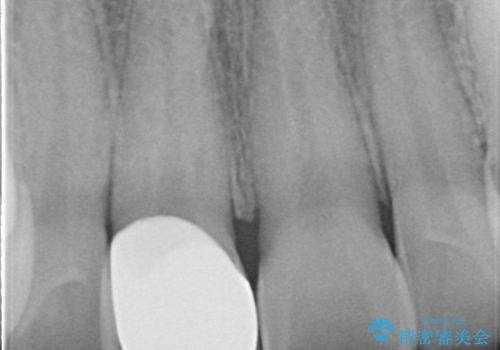

【オールセラミッククラウン】前歯の被せ物

- 矯正後、前歯被せ物のやりかえを希望され治療を行いました。

オールセラミック(スペシャル)にて修復しております。

- 天然歯を削ります